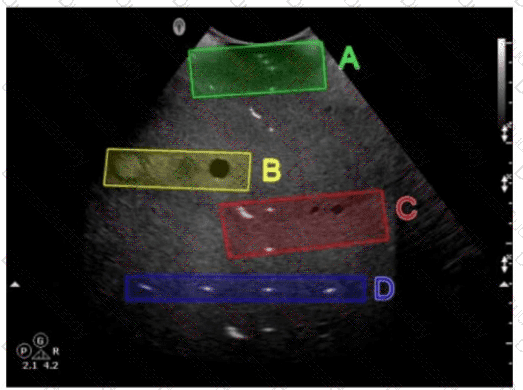

Which target group in this image of a tissue-mimicking phantom is used for gray-scale evaluation?

SPI Question 53

Options:

A.

Option A

B.

Option B

C.

Option C

D.

Option D

Buy Now